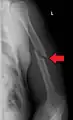

Midshaft humerus fracture with callus formation

Middle

Middle fractures are usually caused by either physical trauma or falls. Physical trauma to the humerus shaft tends to produce transverse fractures whereas falls tend to produce spiral fractures. Metastatic breast cancer may also cause fractures in the humerus shaft.[12] Long spiral fractures of the shaft that are present in children may indicate physical abuse.[5]

Definitive diagnosis of humerus fractures is typically made through radiographic imaging. For proximal fractures, X-rays can be taken from a scapular anteroposterior (AP) view, which takes an image of the front of the shoulder region from an angle, a scapular Y view, which takes an image of the back of the shoulder region from an angle, and an axillar lateral view, which has the patient lie on his or her back, lift the bottom half of the arm up to the side, and have an image taken of the axilla region underneath the shoulder.[9] Fractures of the humerus shaft are usually correctly identified with radiographic images taken from the AP and lateral viewpoints.[12] Damage to the radial nerve from a shaft fracture can be identified by an inability to bend the hand backwards or by decreased sensation in the back of the hand.[5] Images of the distal region are often of poor quality due to the patient being unable to extend the elbow because of pain. If a severe distal fracture is suspected, then a computed tomography (CT) scan can provide greater detail of the fracture. Nondisplaced distal fractures may not be directly visible; they may only be visible due to fat being displaced because of internal bleeding in the elbow.[7]

Fractures of the humerus shaft are most often uncomplicated, closed fractures that require nothing more than pain medicine and wearing a cast or sling. For midshaft fractures up to 12 weeks may be required for healing.[17]